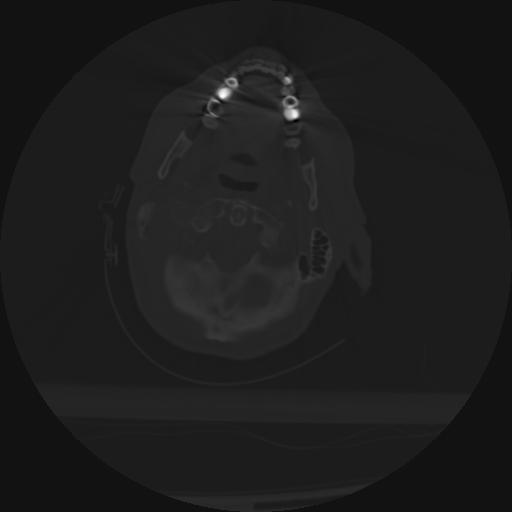

21 ANGIO,CE,Axial,3.0,ANGIO,,